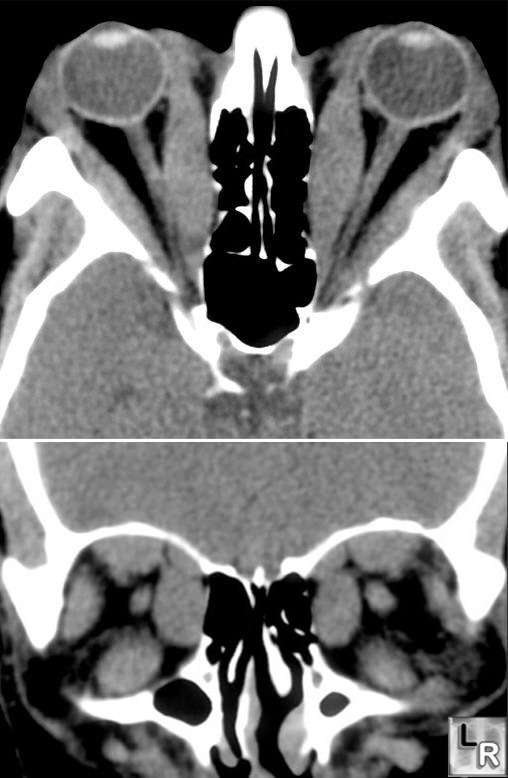

CAT_Scan_Orbital_Muscle_Hypertrophy_GravesLeft Image shows CAT scan of  exopthalmos caused by hypertrophied extra-ocular muscles in Graves Disease.  If severe, the optic nerve can be compromised at the orbital apex resulting in loss of vision.  Antigens in the extraocular muscles and orbital fat may be attacked by the autoimmune disease process.